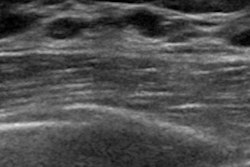

Dense breast tissue is associated with increased risk of breast cancer, and can have a masking effect on mammography, causing some cancers to be missed. Since 2009, more than 30 U.S. states have passed breast density notification laws intended to inform women if they have dense tissue, and if so, to encourage them to discuss supplemental imaging with their doctor.

Ultrasound has been the primary supplemental imaging modality, Dibble's group noted, but its performance has only been assessed after digital mammography, not after DBT -- which due to its 3D nature has been shown to find more cancers than mammography.